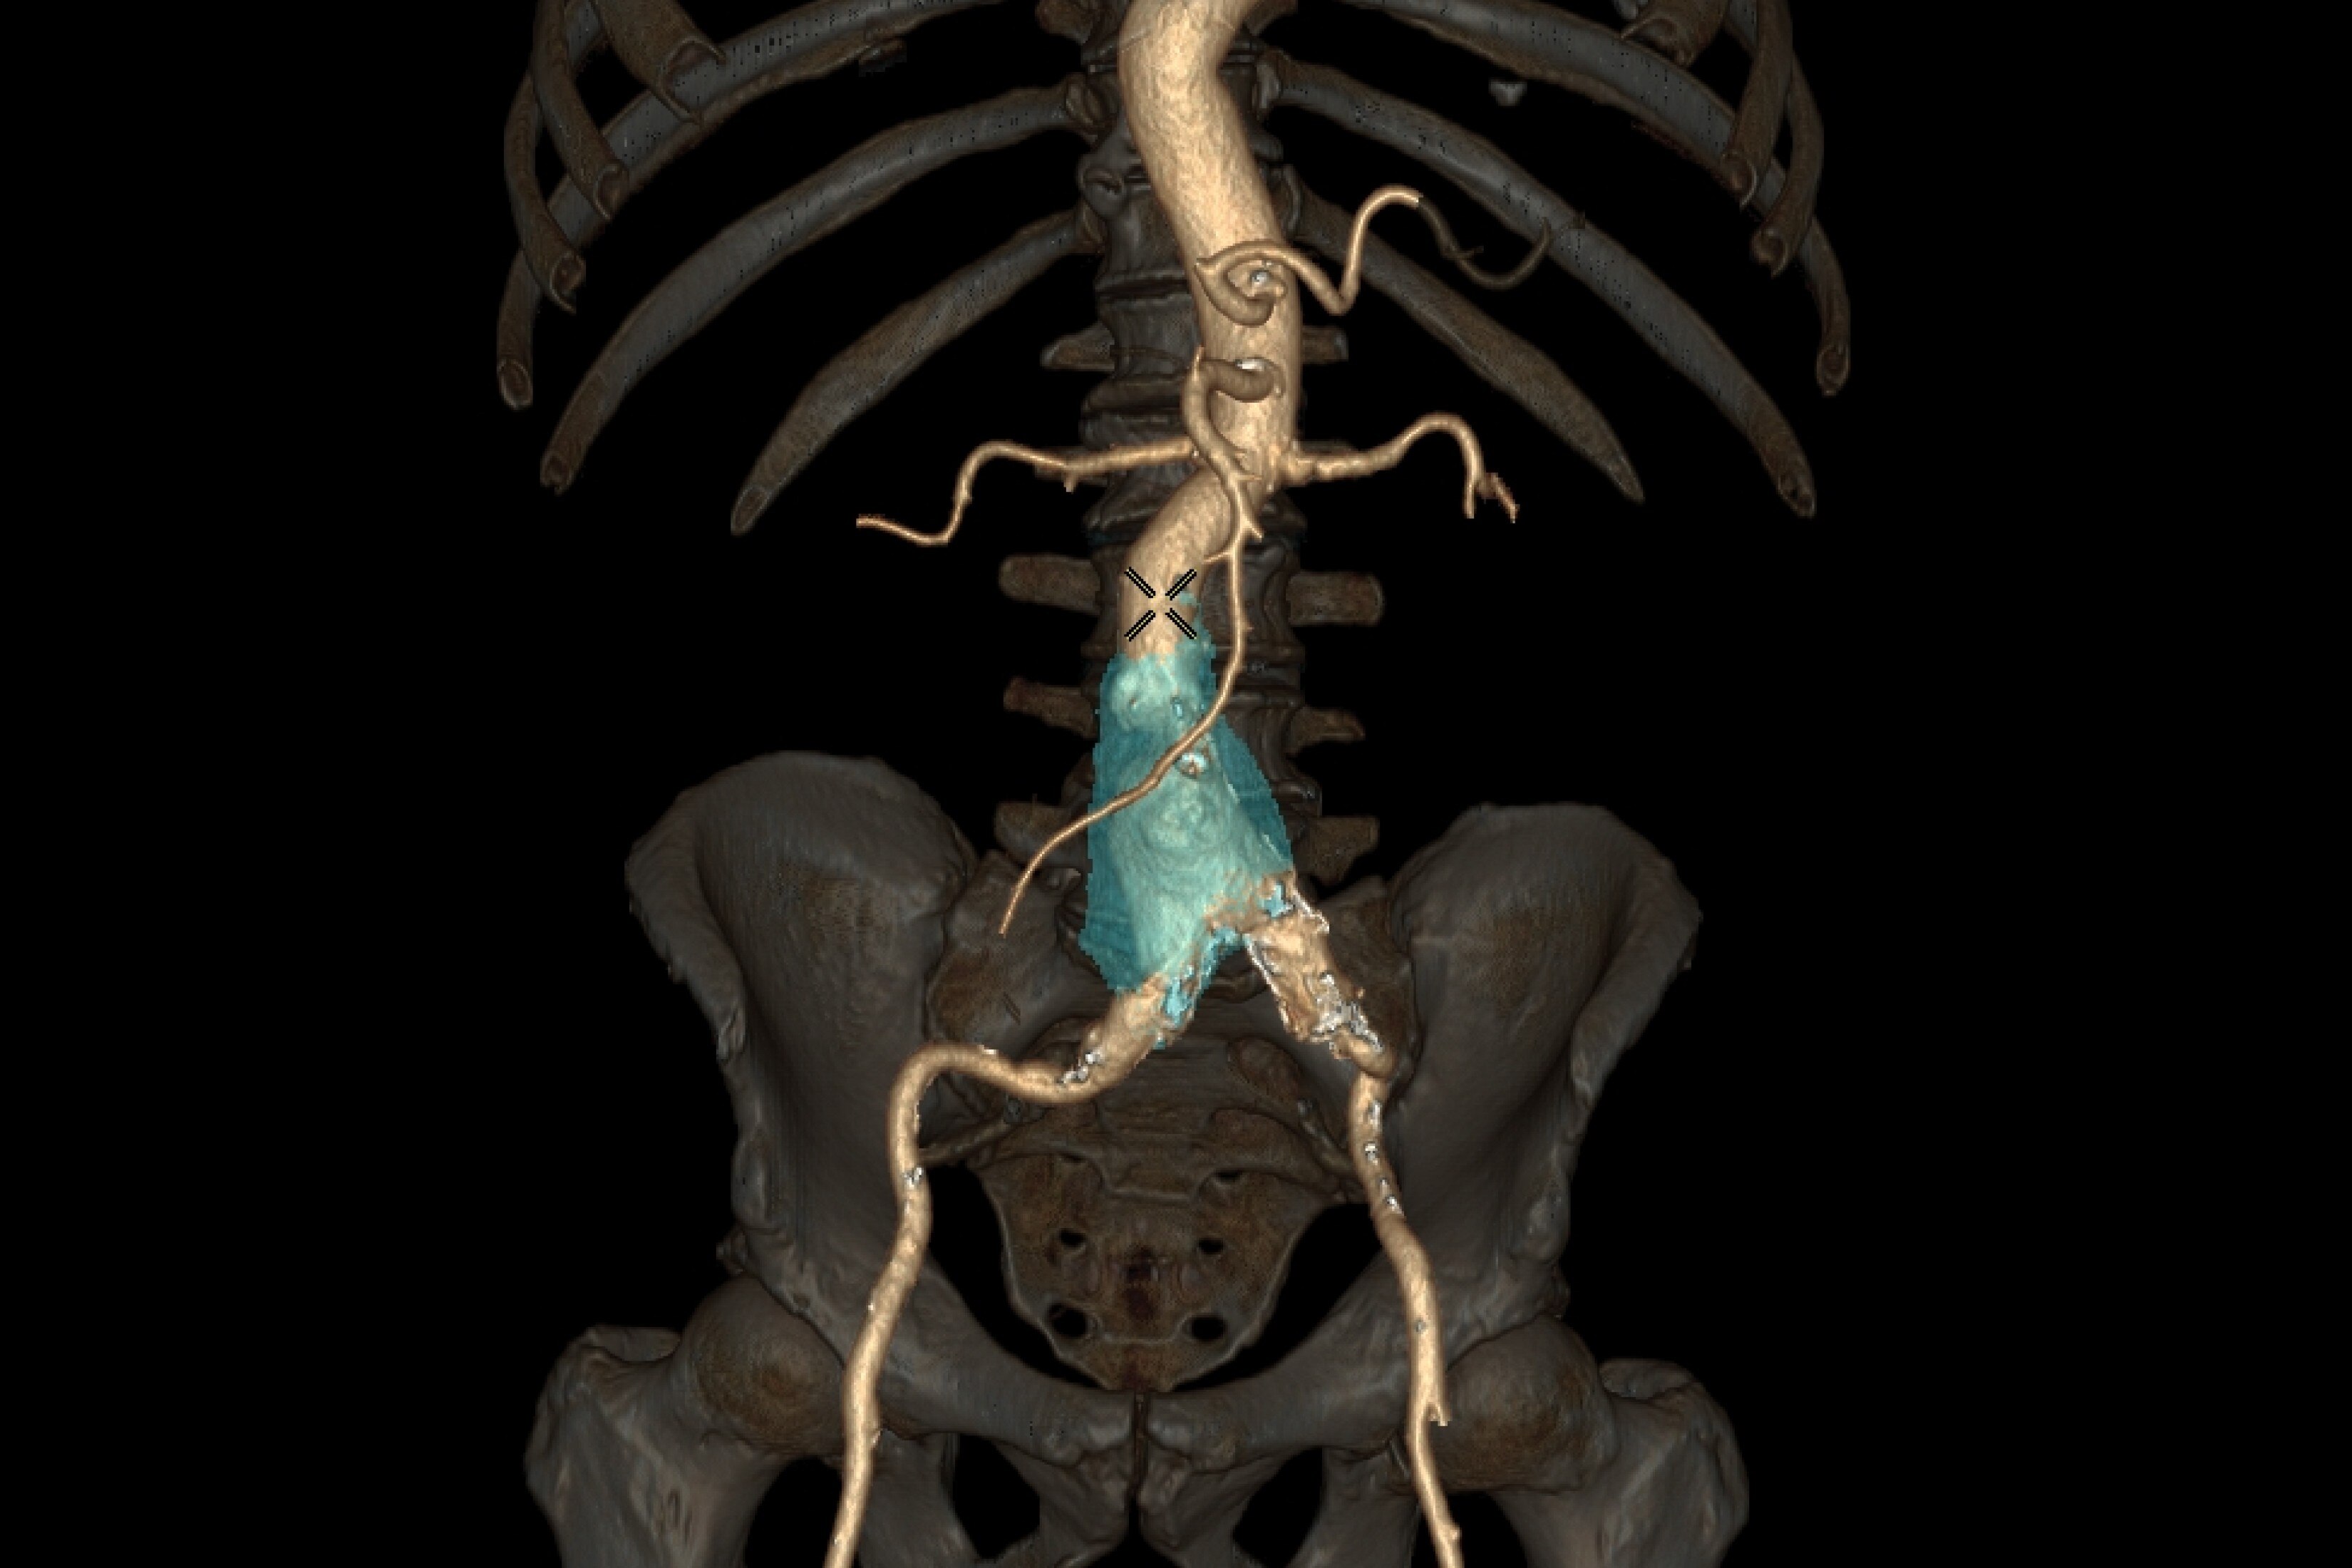

En la RM, los tiempos de adquisición prolongados implican que la adquisición de imágenes se vea comprometida por el movimiento del cuerpo. Hasta ahora. Gracias al aprendizaje profundo, hemos reducido los tiempos de adquisición de minutos a segundos, lo que reduce los artefactos de movimiento y la necesidad de repetir las exploraciones. La aceleración con Sonic DL™ equipa al escáner con la capacidad de igualar la velocidad del cuerpo humano, permitiendo adquisiciones de imágenes que antes no eran posibles.

Construido sobre el éxito revolucionario de AIR™ Recon DL, nuestra primera innovación pionera en la reconstrucción de aprendizaje profundo, Sonic DL™ sigue con audacia sus pasos, avanzando en nuestra misión de revolucionar la RM. El aprendizaje profundo, cuando se aplica a la reducción del tiempo de exploración, convierte los minutos en segundos, lo que ofrece la rapidez de una TC y la calidad de una RM. Es mucho más rápido de lo que permiten las técnicas de aceleración convencionales actuales, lo que ayuda a los radiólogos a realizar diagnósticos precisos desde el principio.

Sonic DL™ permite a los departamentos hacer lo imposible: explorar con precisión a pacientes que antes no se podían explorar de forma eficaz. Ahora, incluso los pacientes enfermos y poco colaboradores pueden someterse a exploraciones en cuestión de segundos, lo que proporciona al personal técnico tiempo libre para realizar el procedimiento con tranquilidad. Al minimizar las posibilidades de movimiento y artefactos que distorsionan las imágenes de exploración, se reduce significativamente la necesidad de volver a realizar exploraciones. Con las exploraciones de un solo latido, los pacientes ya no necesitan contener la respiración, lo que crea una experiencia de exploración más cómoda, tanto para ellos como para el personal técnico que las realiza.